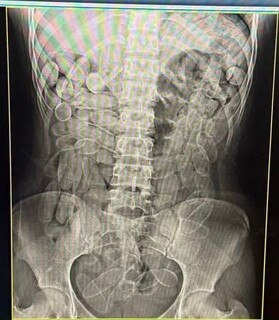

As jovens foram encaminhadas ao hospital da Santa Casa de Corumbá, onde exames de raio-x confirmaram a presença das cápsulas no estômago, totalizando 2,2 quilos. Ambas estão sob custódia no Pronto Socorro local e posteriormente serão encaminhadas à delegacia da Polícia Federal.